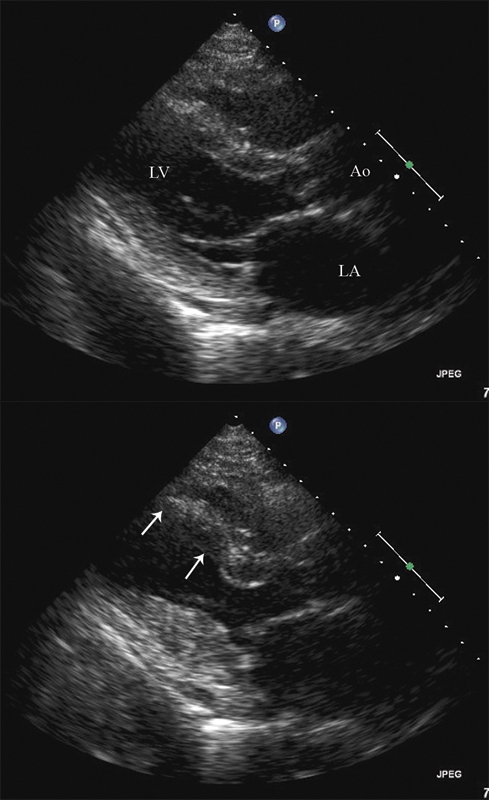

فحوصات تشخيصية لبعض امراض القلب والشرايين التاجية